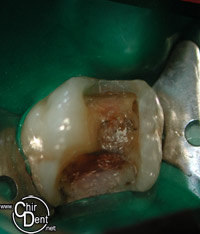

| Dent présentant un pansement et de volumineux amalgames | Une fois débarrassée du tisseux carieux et des anciennes obturations, la cavité est importante | Une pièce en composite ou en céramique est réalisée au laboratoire de prothèse ou usinée. |